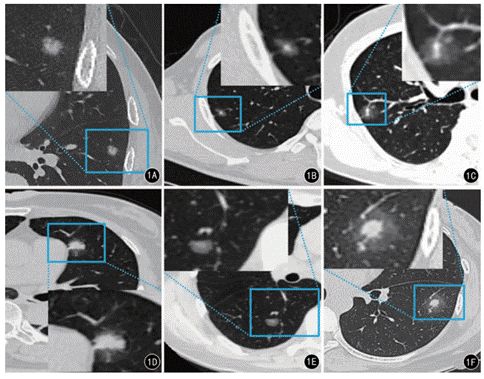

纯磨玻璃结节

单纯磨玻璃结节表现为肺内密度轻微增加,增加程度小于实性改变,呈模糊的云雾状,并可见其内血管和支气管纹理。结节内无实性成分。

• 为类圆形或不规则形态;3gg帝国网站管理系统

• 边缘形态表现为分叶征;3gg帝国网站管理系统

• 瘤肺界面清楚,大多平整光滑,少部分毛糙;3gg帝国网站管理系统

• 内部多伴有气腔隙或充气支气管征;3gg帝国网站管理系统

• 部分病灶周围血管改变或胸膜凹陷。3gg帝国网站管理系统

病灶周围血管改变胸膜凹陷以及有无分叶征表现,是辅助判断结节是否发生浸润的主要征象。随着结节逐渐恶变,分叶征明显增多,结节周围血管因肿瘤侵袭而杂乱无章,并发生胸膜凹陷症状

未浸润结节可留待观察,避免手术对健康肺组织造成伤害。已浸润结节极易恶变为肺腺癌,需尽早手术切除。

混合性磨玻璃结节

混合性磨玻璃结节与纯磨玻璃结节的区别特征,在于实性成分伴磨玻璃密度的晕环。

值得注意的是,混合性结节为恶性的可能性为63%,远大于实性肺结节。

结节中的实性成分越多恶性的可能性就越大。因此,对混合性结节千万不可掉以轻心。

实性肺结节3gg帝国网站管理系统

实性结节是肺内圆形或类圆形密度增高,病变密度足以掩盖其中走行的血管和支气管。

实性结节多见于肺癌,但是也可见于良性疾病,如肺错构瘤炎性假瘤等。有钙化及脂肪密度提示良性概率较大。

除了通过结节直径预测良恶性之外,我们还可通过毛刺征与血管集束征来预测结节的良恶。在结节大于1cm时,建议穿刺活检明确诊断,以绝后患。

针对直径不大的肺结节,目前常用的处理方法还是观察随访。如果结节短期内有明显增大,需要明确诊断后再进行手术切除。这样就能达到一种既不会耽误病情,同时也不会过度治疗的目的,实现对肺结节的有效应对。